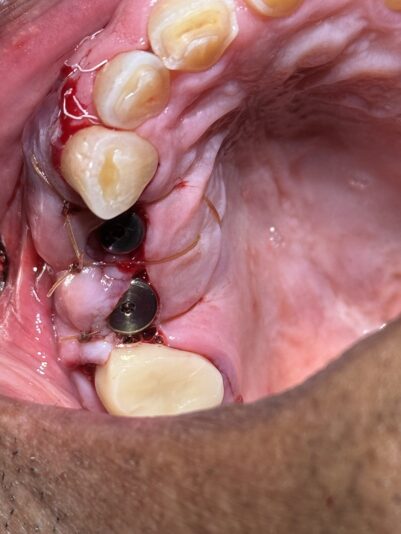

• Here is an update from the previous post…

This shows how we dealt with the complication of a buccal perforation. Luckily, the patient had sufficient width so we removed the implant and placed another implant lingual to that site with better buccal lingual agulation. We then bone grafted the site and perforation and secured a resorbable collagen…

Read more